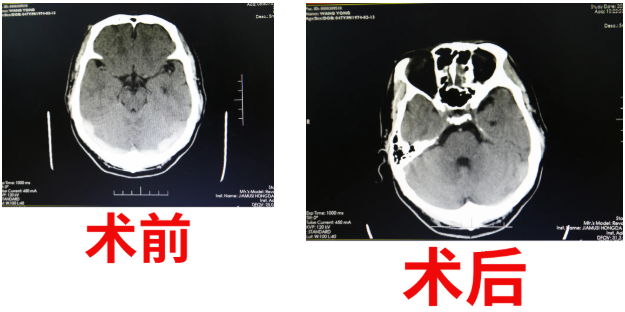

治療顱內(nèi)靜脈竇血栓就是在與時間賽跑,這對挽救患者的生命及神經(jīng)功能的恢復至關重要。在與患者家屬充分溝通后,患者被迅速送入介入導管室。手術中,艾主任帶領腦血管病介入團隊攻克重重難點,用那根承載著生命安全的導絲開啟了他們工作的又一次挑戰(zhàn)!艾主任密切注視顯示屏,嫻熟地通過患者大腿根部2mm切口將抽吸導管及球囊擴張導管送入顱內(nèi)靜脈竇,取出大量血栓實現(xiàn)顱內(nèi)靜脈竇血管再通,憑借著醫(yī)護人員嫻熟的手術技巧和豐富的經(jīng)驗,原本無法回流的靜脈開始通暢。

盡管醫(yī)生們穿著沉重的鉛衣奮戰(zhàn),但看到患者的顱內(nèi)靜脈竇血管成功開通的那一瞬間,在場醫(yī)護人員滿滿的喜悅充斥著手術室每個角落。細節(jié)決定成敗,艾主任準確把握適應癥、術前縝密計劃、術中謹慎操作,介入室護士嚴密監(jiān)護,麻醉師的精湛技術,手術團隊完美配合,在2小時內(nèi)“生命之流”就被重新開通,王先生順利轉回普通病房。

術后給與患者抗凝、改善循環(huán)等對癥治療。在腦血管病介入科醫(yī)護人員的精心治療及護理下,第二日頭痛癥狀完全消失,復查頭部核磁MRV提示靜脈竇通暢,患者凝血等檢驗項目比值逐漸恢復正常值。患者家屬喜極而泣,拉住艾主任的手激動說道:“我們真是撿回了一條命,沒想到能恢復這么好,感謝佳木斯大學宏大醫(yī)院腦血管病介入團隊,給了我丈夫新生,也給了我們?nèi)胰诵律南M?,要不以后的日子我們真不知道怎么過了!”。這一幕,作為醫(yī)務工作者,內(nèi)心都會感到無比的喜悅,這是手術成功后的喜悅,也是為生命得以延續(xù)而喜悅。